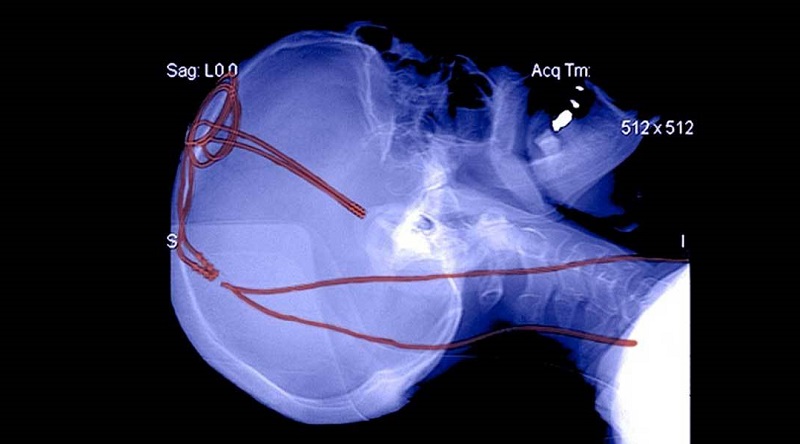

En este caso, lo que estimulamos son partes específicas del cerebro usando una especie de ‘marcapasos cerebral’ de cara a aliviar movimientos como los producidos por el Parkinson o desórdenes afectivos como el sufrimiento crónico. Igualmente se está estudiando como tratamiento para la depresión, la epilepsia o el síndrome obsesivo-compulsivo.

Típicamente constan de una guía (‘lead‘) terminada en los electrodos estimuladores, y situados dentro del cerebro, un generador de pulsos y un cable conector que une ese generador de pulsos con la guía.

La guía y sus electrodos se implantan en diferentes partes del cerebro dependiendo de aquello que se quiera tratar. El generador de pulsos produce pulsos de estimulación a una frecuencia fija y adaptada a las necesidades del paciente.

Los riesgos asociados a esta técnica son las posibles infecciones o sangrados, complicaciones en la cirugía y algún posible efecto colateral como alucinaciones o comportamientos compulsivos. A pesar de ello, se puede considerar una técnica bastante exitosa y con mucho futuro.